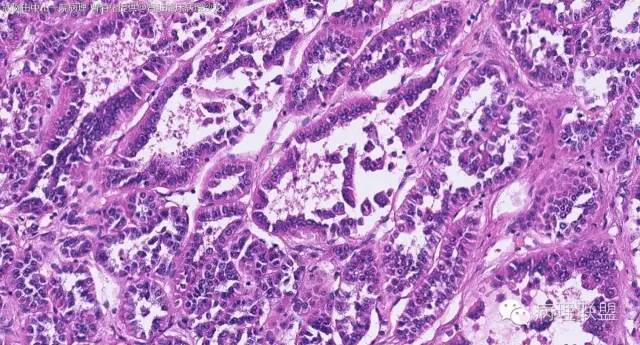

女性,50岁,肾上腺肿物(影像及手术均确认肿物位于肾上腺,界限清楚)。血压升高。(病例由 中山一院病理 曹清华提供,致谢!)

病例讨论

伴假腺样结构的肾上腺皮质腺瘤,合并髓脂肪瘤

从肿瘤的位置及镜下与肾上腺皮质的关系看,应该像是皮质来源肿瘤。假腺样结构的皮质腺瘤没有见过,似乎文献也还没查到。另外inhibina, melanA, syn均阴性(肿瘤旁正常皮质阳)感觉有点迷惑。。。请老师指教,有相关文献么?@武警嘉兴医院 周泉

假腺样是细胞粘附性差了导致。往往可以伴随黏液成分,组化上这几个抗体应该至少会有灶性阳性。

这个我再仔细看下。但,我们这例腺管结构不像是粘附差所致,是真的腺管;间质目前还没有看到有间质粘液变性区域;inhibina, syn, menlana是真的不阳,灶性都没有...